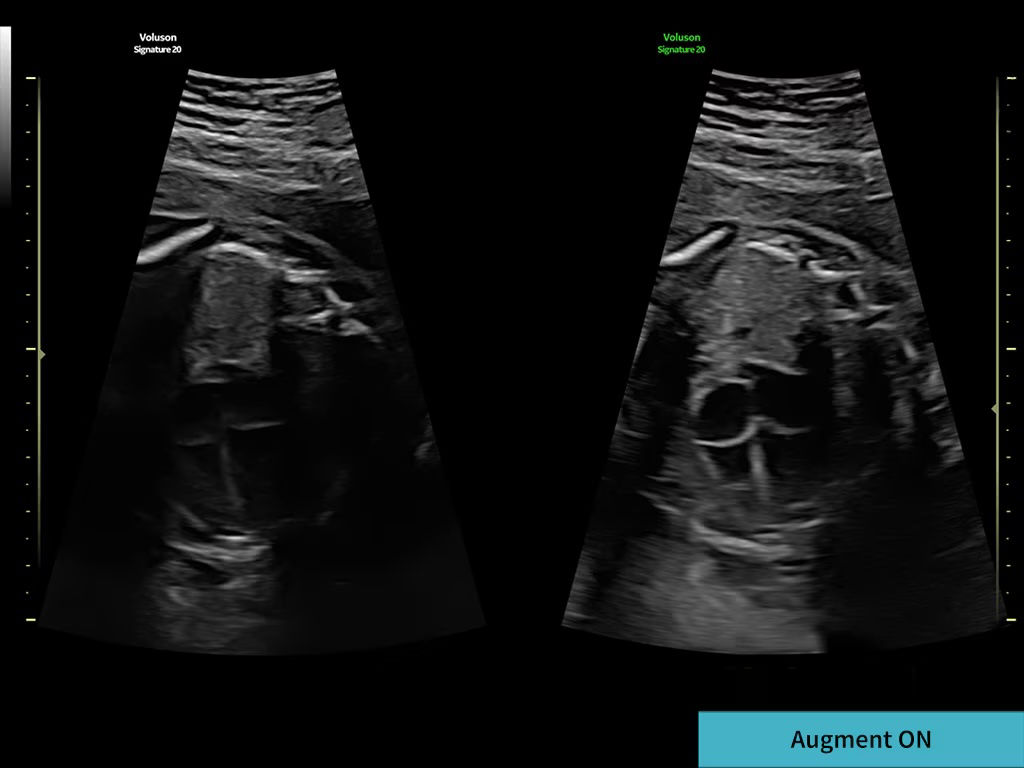

Decreases shadows on B-mode imaging which can obscure adjacent structures by helping to restore tissue information and borders.

With one button touch, reduce noise and increase penetration in even the most challenging, high BMI patients for a clean, robust, homogeneous image.